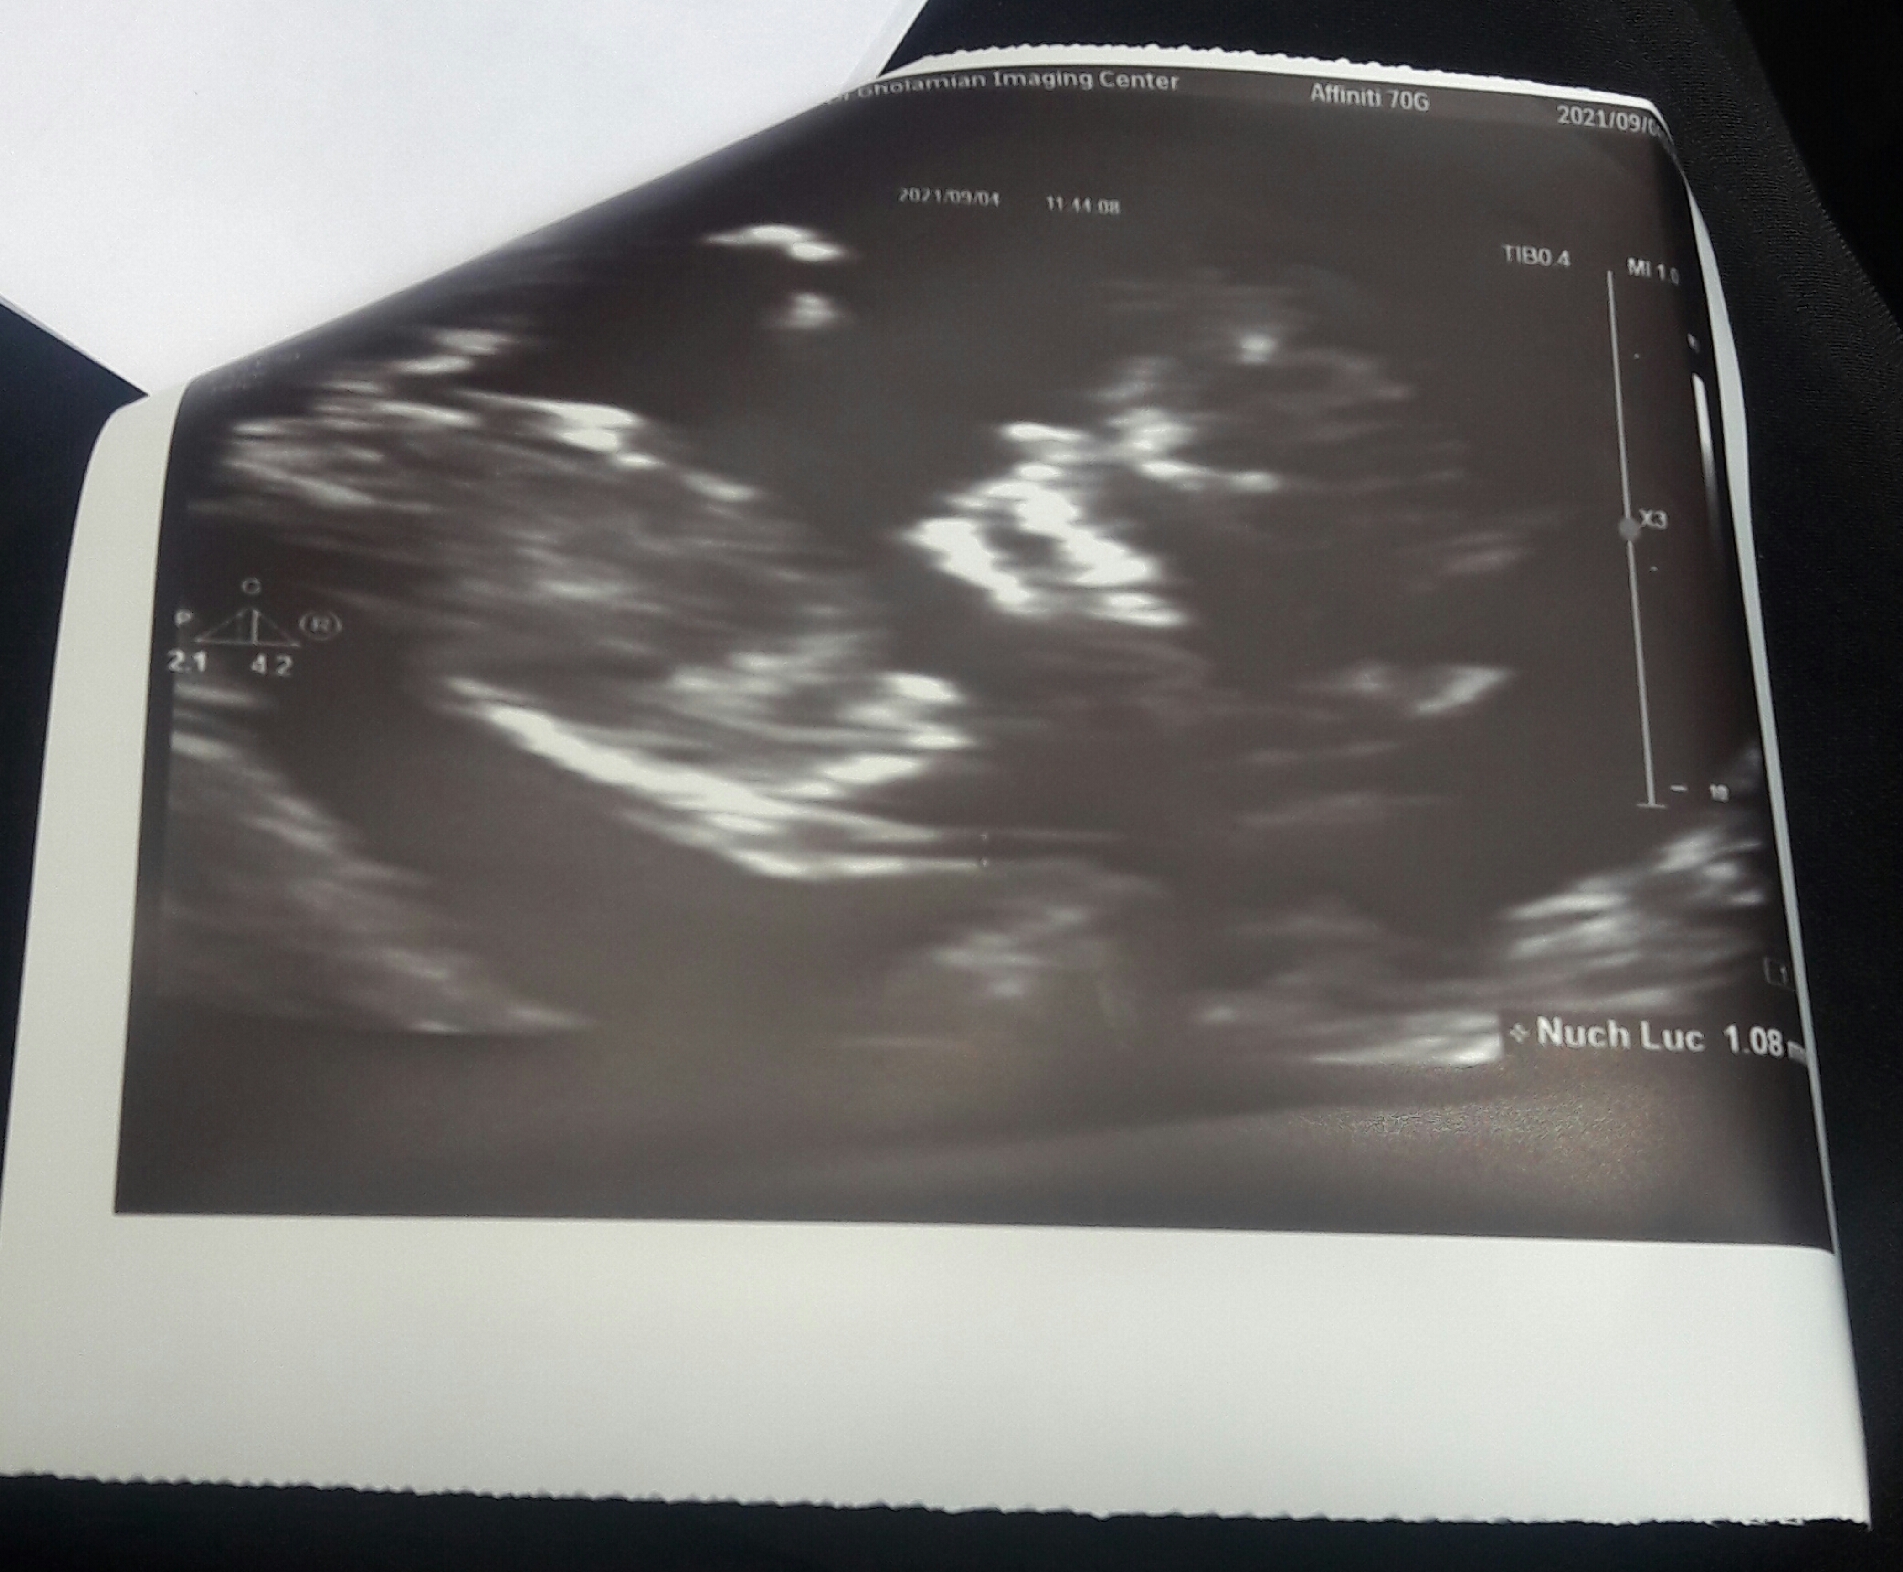

منم ۱۲هفته رفتم ۶۰درصداحتما دختر ۴۰درصدپسره خیلی دوست داشتم بگه ۱۰۰درصدپسره شمابلدین ازروی جمجمه بگ ...

منم ی پسر داشتم این یکی رفتم ان تی گفت پسره

امیدوارم تا سونوی بعدی جنسیتش عوض بشه😑😑وای کاش زود تر سونوی خودمم ببینم از رو ویارم که با پسرم متفاوت بود میگم دختره😞

خدارو چه دیدی شایدم پسر شد۱۶هفته صد درصد معلومه از پایین تنه اش عکس نداری